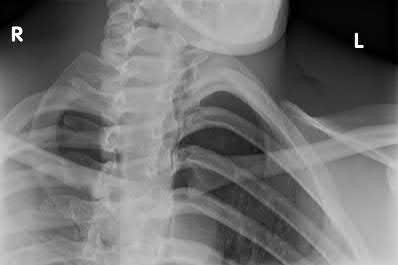

Question 5:

A 45-year-old male is involved in a high-speed motor vehicle collision and presents with the cervical spine radiograph findings typical of traumatic spondylolisthesis of the axis. Which of the following describes the primary mechanism of injury for this specific fracture pattern (Hangman's fracture)?

Correct Answer: Hyperextension and axial loading

Explanation:

A 'Hangman's fracture' is a traumatic spondylolisthesis of the axis (C2) involving fractures through the pars interarticularis. The classical mechanism of injury in modern trauma (e.g., unrestrained passenger hitting the windshield) is hyperextension and axial loading. Flexion-distraction typically causes Chance fractures, while flexion-compression typically causes anterior wedge or teardrop fractures.